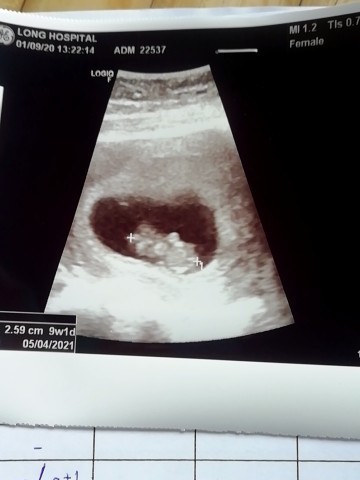

ตั้งท้อง6สัปดาห์ อัตเตอร์ซาวไปแล้วไม่เห็นตัวอ่อน ปกติใมครับ

ไม่เห็นตัวอ่อน

ยังท้องอ่อน ๆ อยู่ / เดี๋ยวก็เจอค่าา ^^

บ้านนี้7วีค เจอแต่หัวใจค่าาาาา

เราเห็นตอน10week ค่ะน้องเล็กมาก

น้องอาจจะยังตัวเล็กอยู่ค่ะ

ปกติจ้า ต้องรอ 2เดือนขึ้นไป

เจอหัวใจตอน9สัปดาห์จ้ะ

11สัปดาห์ ยังไม่เจอเลยค่ะ

บ้านนี้เจอตอน10วีคค่ะ

บ้านนี้เจอตอน 8 วีคค่ะ